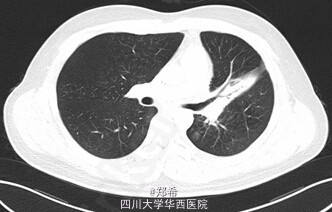

患者21岁,因“咳嗽、咳痰1+年”入院。患者于1+年前无明显诱因出现咳嗽、咳痰,咳黄色脓痰,量少,伴潮热盗汗,于当地医院住院治疗,活检示:支气管内膜结核(具体报告未见),遂予一线抗结核药物治疗,半年后于我院呼吸内科住院调整为二线抗结核药。6+月前因“支气管结核狭窄”于外院安置左主支气管支架,后多次于复查纤支镜取支气管支架均未取出,并于我院查TB-DNA阴性。于1-月前查胸部增强CT示:左肺上叶舌段实变肺不张,作肺内散在斑片条索影,左主支气管内见高密度支架影,支架内可见少许软组织密度影,其远端左主支气管管壁稍厚,多系炎症;左肺门淋巴结增大;心包少量积液;左侧胸膜增厚,左侧胸腔少量积液。查体:左肺呼吸音低。初步诊断:1、左主支气管狭窄2、左主支气管支架置入术后3、支气管内膜结核4、糖尿病。处理:全麻下行左主支气管支架取出+左全肺切除术。手术顺利,术后入ICU继续治疗。讨论:肺结核最严重的并发症之一就是能够引起支气管狭窄,支气管胸膜瘘,因此,要按照结核治疗标准早期、规律、全程、联合用药,此病例属于典型结核引起支气管狭窄,最后不得不切除全肺。